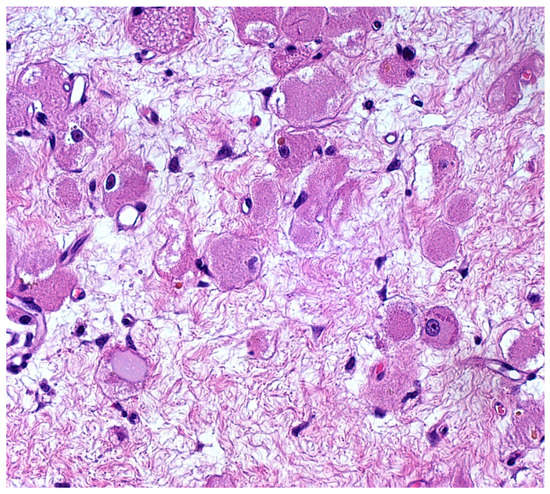

Figure 4. Nuclear atypia was absent to mild. Indeed, the large- to medium-sized tumor cells showed relatively monomorphic, peripherally or centrally located, vesicular nuclei of small to medium size; the chromatin was fine, despite occasional slight variation in nuclear size and shape, with irregularities of nuclear membranes and rare multinucleations. The nucleoli were occasionally evident, but small. Pleomorphism, mitoses and necrosis were absent. The intercellular stroma was almost virtual in the majority of the tumor, but loose connective tissue (no desmoplasia) was found in less-cellular areas (like this one) (Hematoxylin and Eosin, 20×; previously unpublished, original photo).